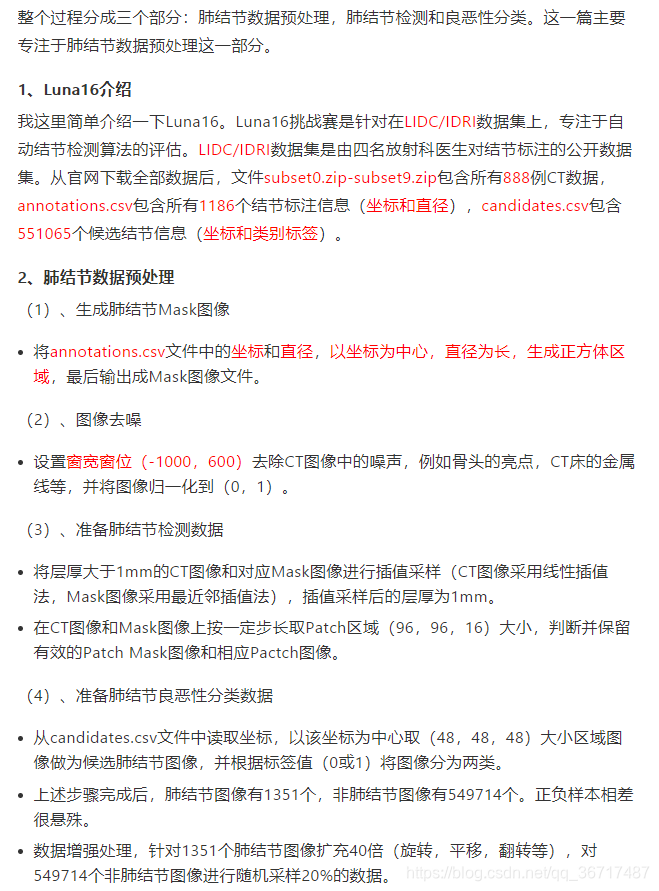

Luna16——肺结节检测和良恶性分类挑战赛(一)